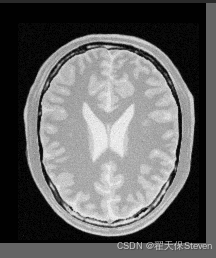

配准后图像